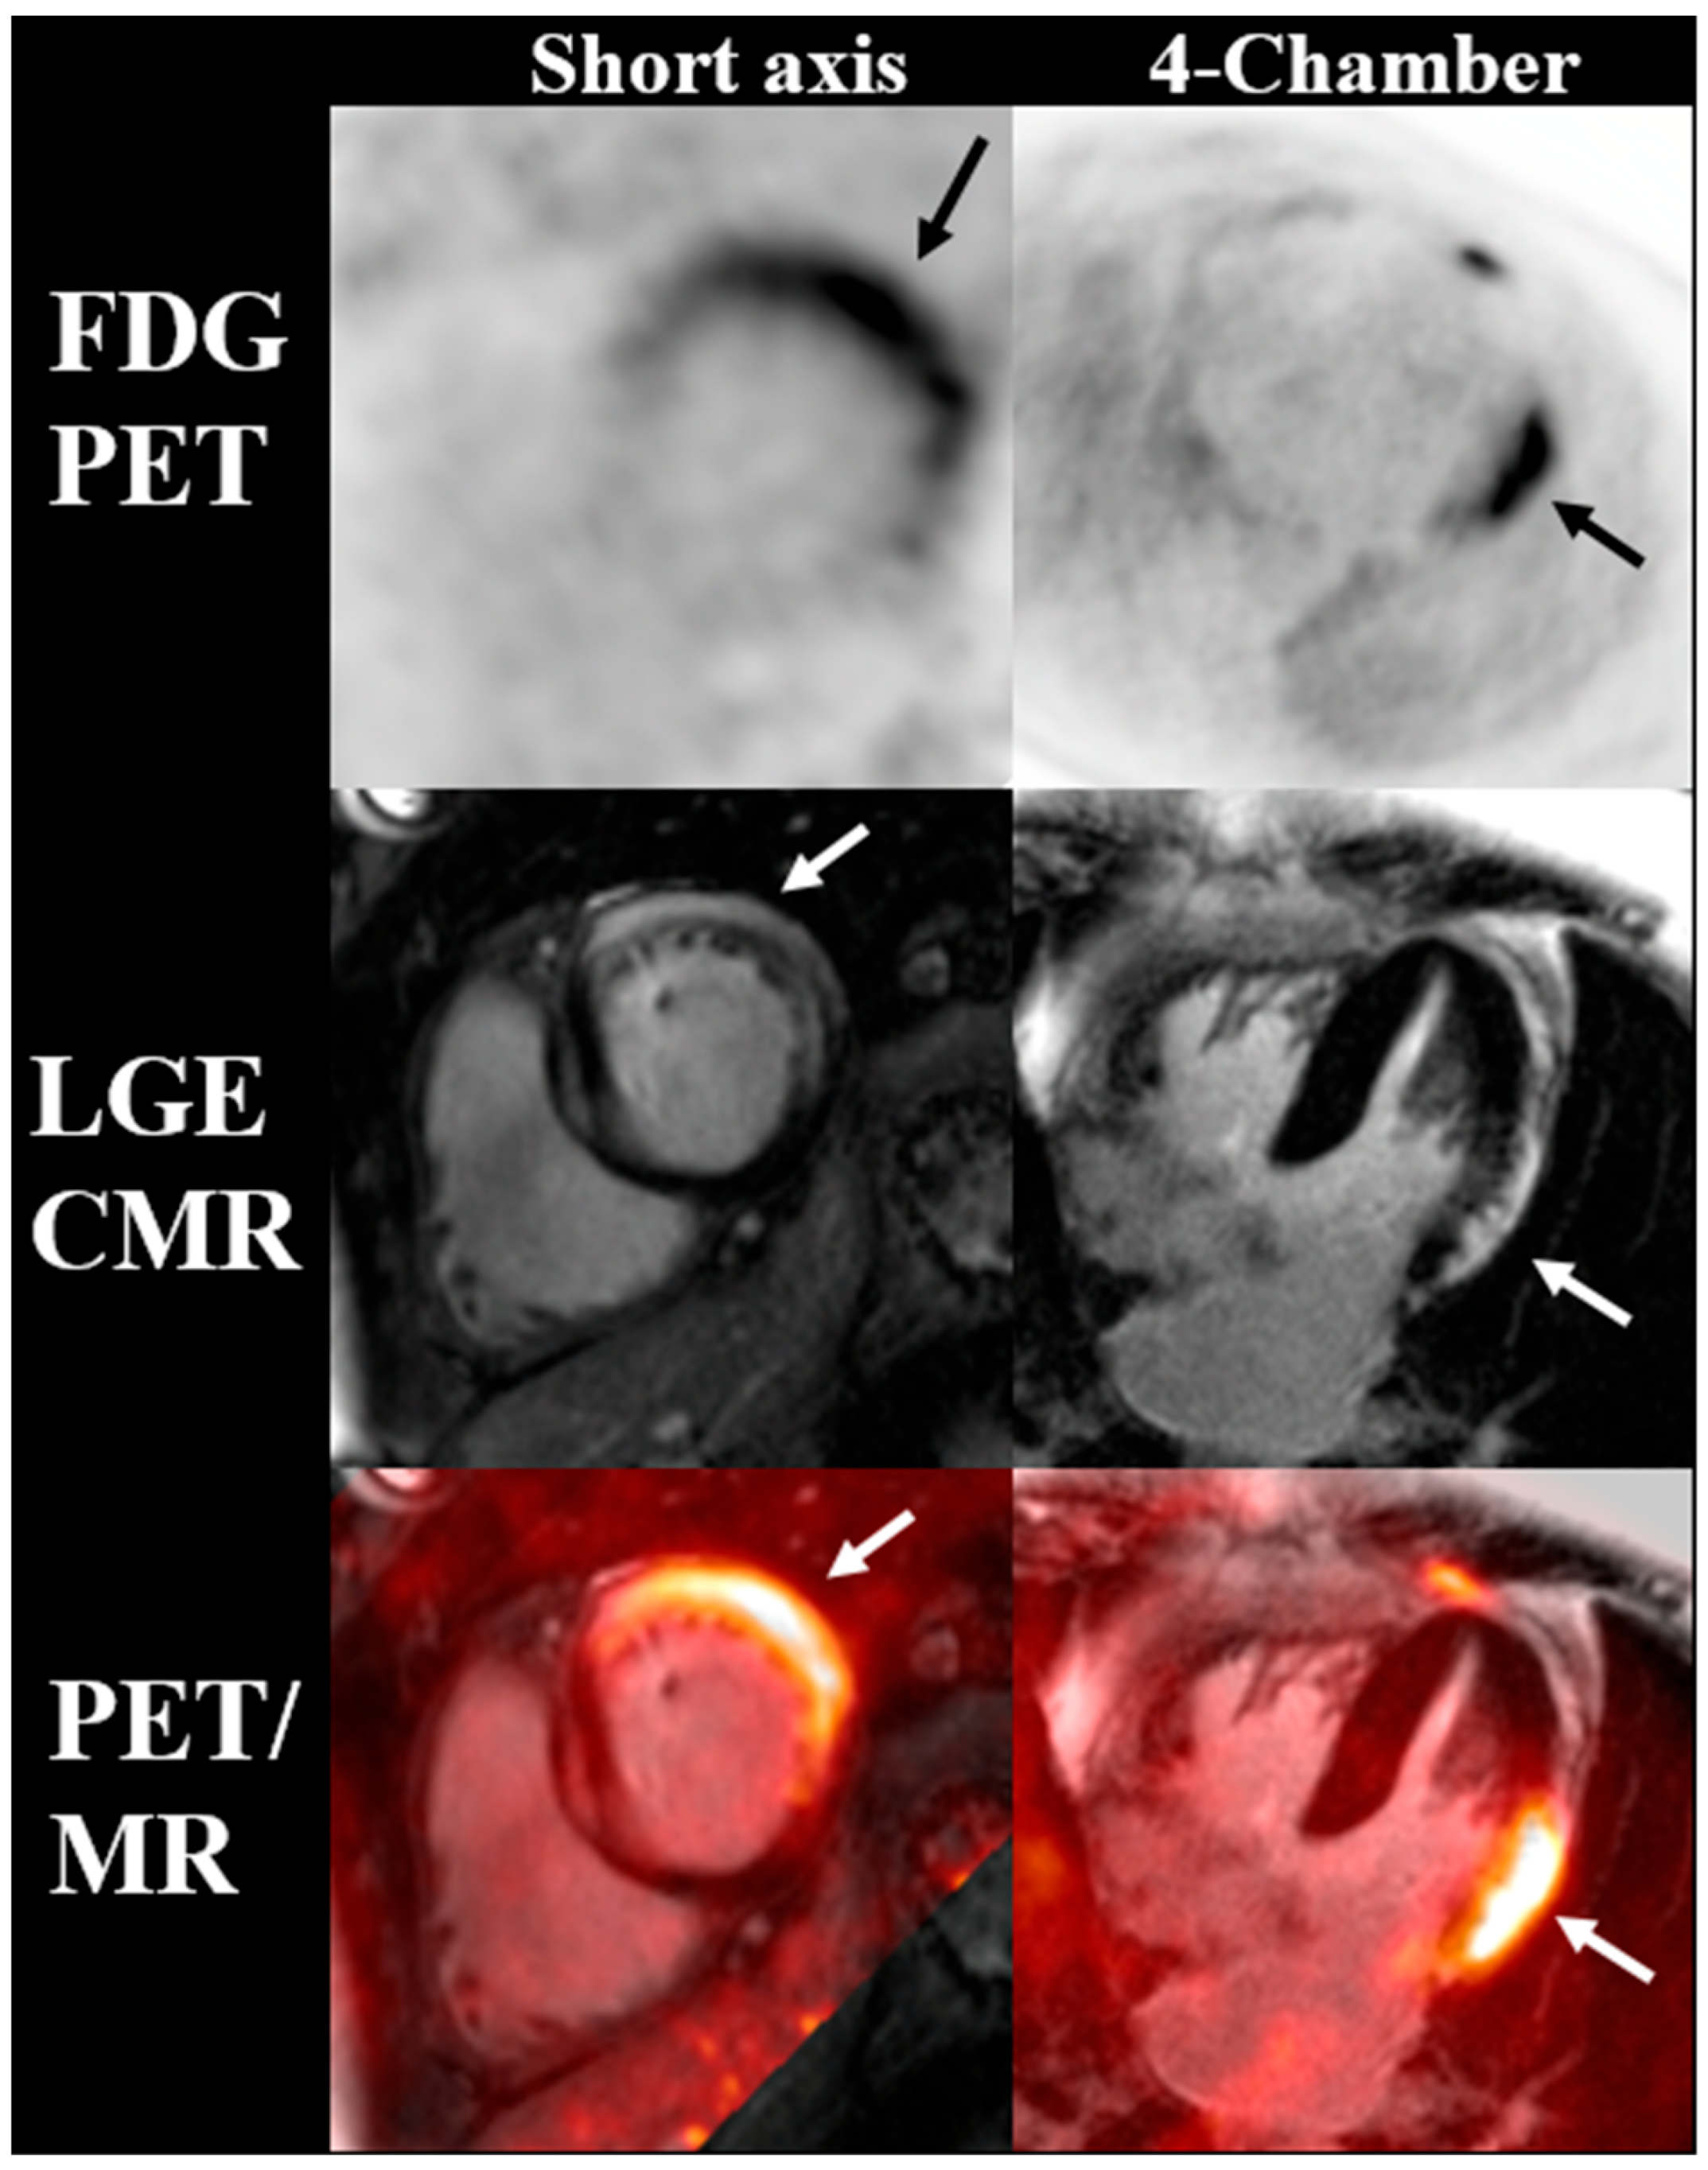

- Rischpler, C.; Rassaf, T.; Umutlu, L.; Herrmann, K.; Schlosser, T.-W.; Totzeck, M. Imaging the Inflammatory Response in Checkpoint Inhibition Myocarditis. J. Nucl. Med. 2021, 63, 14–16. [Google Scholar] [CrossRef]

- Arponen, O.; Skyttä, T. Immune checkpoint inhibitor-induced myocarditis not visible with cardiac magnetic resonance imaging but detected with PET-CT: A case report. Acta Oncol. 2020, 59, 490–492. [Google Scholar] [CrossRef]

- Nensa, F.; Kloth, J.; Tezgah, E.; Poeppel, T.D.; Heusch, P.; Goebel, J.; Nassenstein, K.; Schlosser, T. Feasibility of FDG-PET in myocarditis: Comparison to CMR using integrated PET/MRI. J. Nucl. Cardiol. Off. Publ. Am. Soc. Nucl. Cardiol. 2018, 25, 785–794. [Google Scholar] [CrossRef]